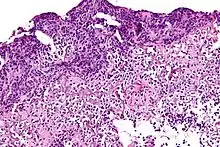

![]() | Squamous cell carcinoma of cervix | Invasive Squamous Carcinoma of the Cervix. Cold Knife Cone. | Category: Histopathology of squamous cell carcinoma of the cervix | Invasive squamous carcinoma of cervix |